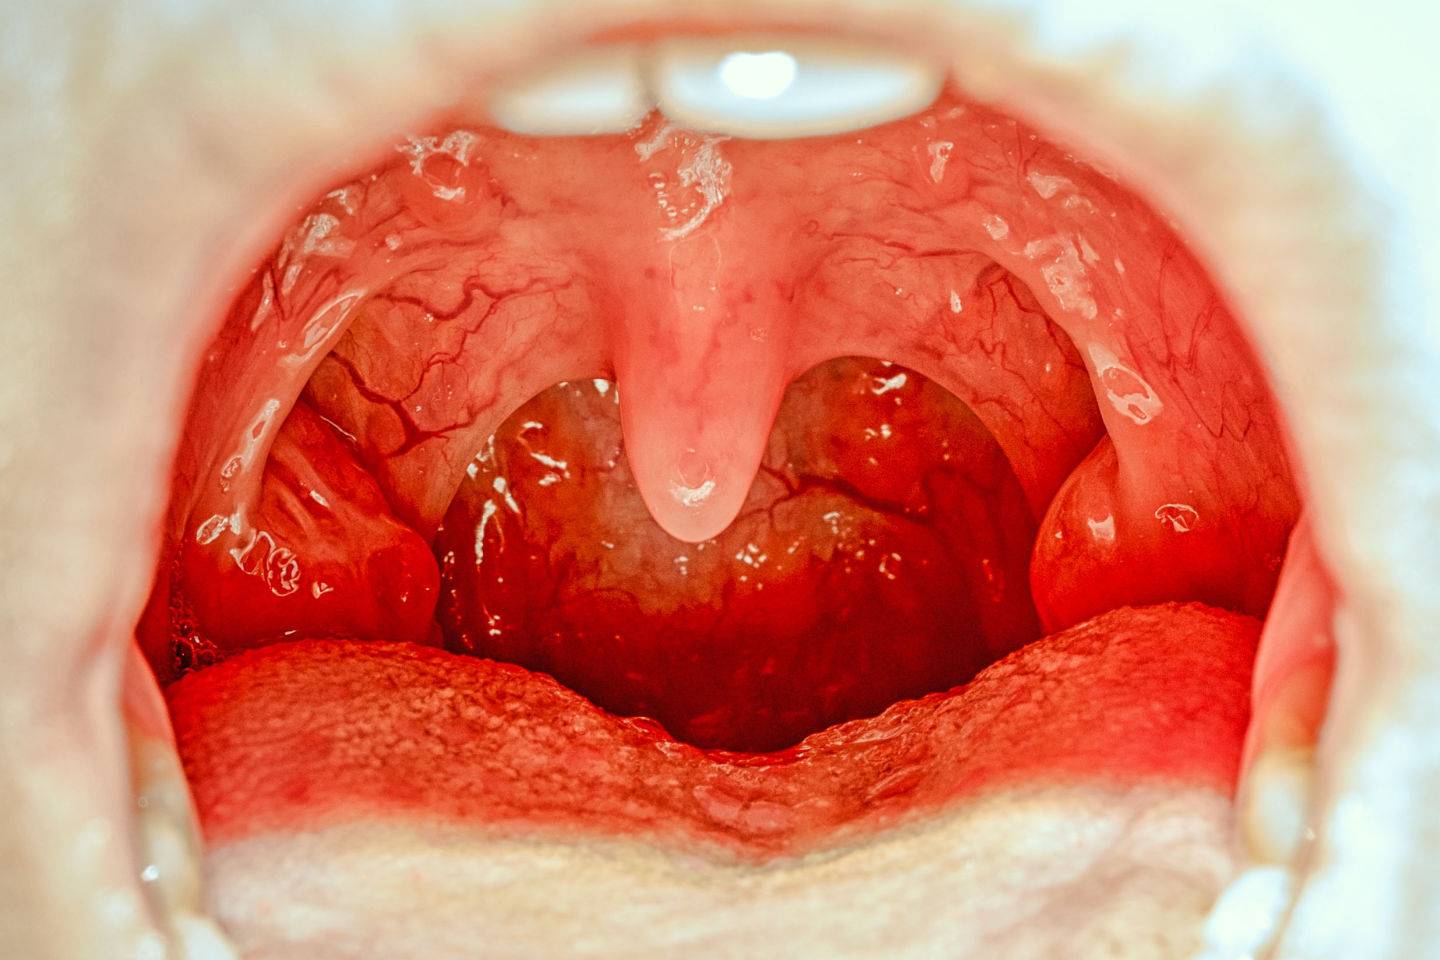

Grgljanje slane vode je još jedan jednostavan i efikasan način za ublažavanje boli u grlu. Ova metoda djeluje tako što slani rastvor pomaže u ispiranju bakterija i virusa iz grla, smanjujući tako upalu i iritaciju. Da biste pripremili slanu vodu, jednostavno rastvorite pola kašičice soli u čaši tople vode i grgljajte nekoliko puta dnevno. Ovaj tretman je prirodan, jednostavan i siguran za korištenje. Mnogi ljudi su izvijestili o značajnom poboljšanju simptoma nakon nekoliko dana redovnog grgljanja. Slana voda može također pomoći u smanjenju otoka i nelagode, čineći ovaj tretman posebno korisnim u ranim fazama infekcija grla.